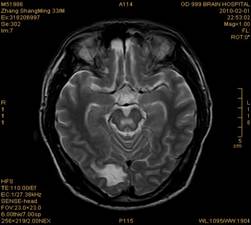

案例1 患者,男,33岁, 海洛因脑病的头颅MR。表现为双侧大脑后部皮层下白质、双侧内囊后肢、枕叶白质、胼胝体压部、中脑、桥脑、双侧小脑半球齿状核质及双侧桥臂多发对称性片状及斑片状长T1长T2异常信号影,FLAIR序列呈高信号,其中双侧内囊后肢表现为特异的“八字征”,双侧小脑半球齿状

核质表现为对称的“蝶翼征”,脑干病变呈“蟹钳征”及“中空征”。增强后双侧半卵圆中心、双侧枕叶白质及双侧小脑半球病变内或边缘中度强化影。给予患者抗炎、脱水、疏通血管及营养神经等药物治疗,一个月后痊愈出院。